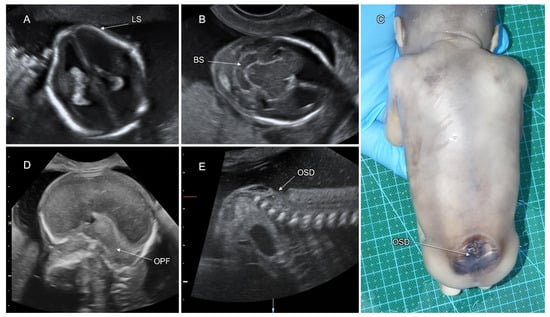

3.2. Spinal Dysraphism

| Spinal dysraphism | 2–16% |

| OSD # outcomes: